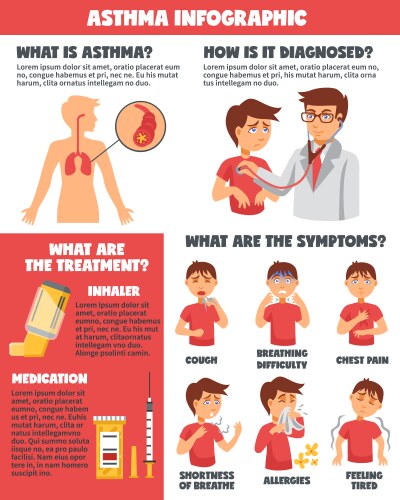

- Asthma

- Infographic

- Diagnosis

- Medication

- Treatment

- Cough

- Symptom